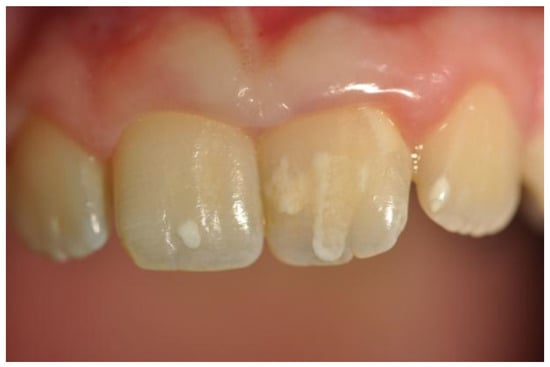

Twenty-four CD patients reported recurrence of aphthosis before the CD diagnosis, while only two patients had had two aphthosis episodes within one year of diagnosis. No patient or control had aphthosis at the time of the dental examination. Dental enamel disorders were reported in seven celiac patients (14.3%) and in 0 controls (p = 0.002). In particular, four patients had a grade 1, according to Aine classification (defects in color of enamel, single or multiple cream, yellow, or brown opacities with clearly defined or diffuse margins), and three had a grade 2 according to Aine (slight structural defects, rough enamel surface filled with horizontal grooves or shallow pits) (see Table 1). As enamel hypoplasia is a sign of early gluten damage (before teething), we compared the age at diagnosis between those with and without enamel hypoplasia, but we did not observe any significant statistical difference between them (25.6 ± 10.6 vs. 22.48 ± 13.4, p = 0.5). None had atrophic glossitis at the time of the oral examination. During the dental examination, we accidentally found that nine CD patients (18.3%) and three (5.9%) controls (p = 0.05) showed non-specific tooth wear (see Table 1), characterized by loss of mineralized tooth tissue, unrelated to bacterial demineralization action. We adopted the Smith and Knight tooth wear index to classify these lesions [14].

Following this classification we observed: Score 1 (loss of enamel characteristics) in four CD patients, Score 2 (exposing dentine for less than one-third of surface) in three, Score 3 (exposing dentine for more than one-third of surface) in two (Figure 3). In the control group, we only found three patients with tooth wear, all classified as Score 1.

Figure 3. A case of tooth wear in a celiac disease (CD) patient (Score 3).